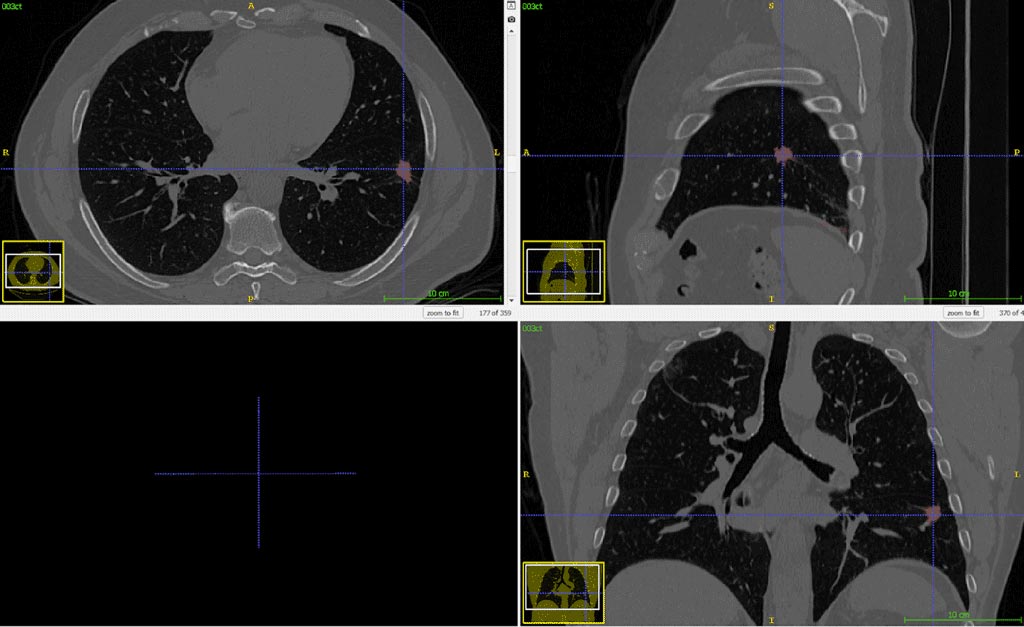

Medical experts can visually identify nodules on a CT scan, but they need to rely on computerized analysis to estimate shape and volume of nodules, as well as their progression over time. It is visually easier to identify nodules than lung tumors, since the former are supposed to have an elliptical shape, while the chromatic aspect of the latter is difficult to distinguish from healthy tissues on a CT image. This difference reflects also on the annotation phase: it will be easier for a non-expert annotator to identify a tumor than a nodule.

Our client needed an automatic process of lung nodules and tumors segmentation to deal with this difficulty in a way that is quick to perform and memory efficient. Our methodology (once built around graph cuts algorithms) currently focuses on Deep Learning with neural networks. Their advantages are multiple: besides offering a much faster segmentation, this is a fully automated solution, able to automatically detect all tumors and nodules, with no need for external intervention. This solution proves to provide a simple and effective answer to many problems of medical segmentation. It is robust and practical, as it solves the challenges fast and efficiently. We at RSIP Vision (and not only us) consider it the best approach to perform nodule and tumor detection and segmentation in lung CT images.

Compared with hand-made nodule segmentation in the lung (performed by an expert), this automatic lung nodules and tumors segmentation method grants results which are very close to the (much slower) manual segmentation. It also enables our client to overcome the difficulty of tumors and healthy tissues appearing on the CT scan in a very similar range of intensity values. You can read here about other projects led by RSIP Vision in the field of pulmonology.